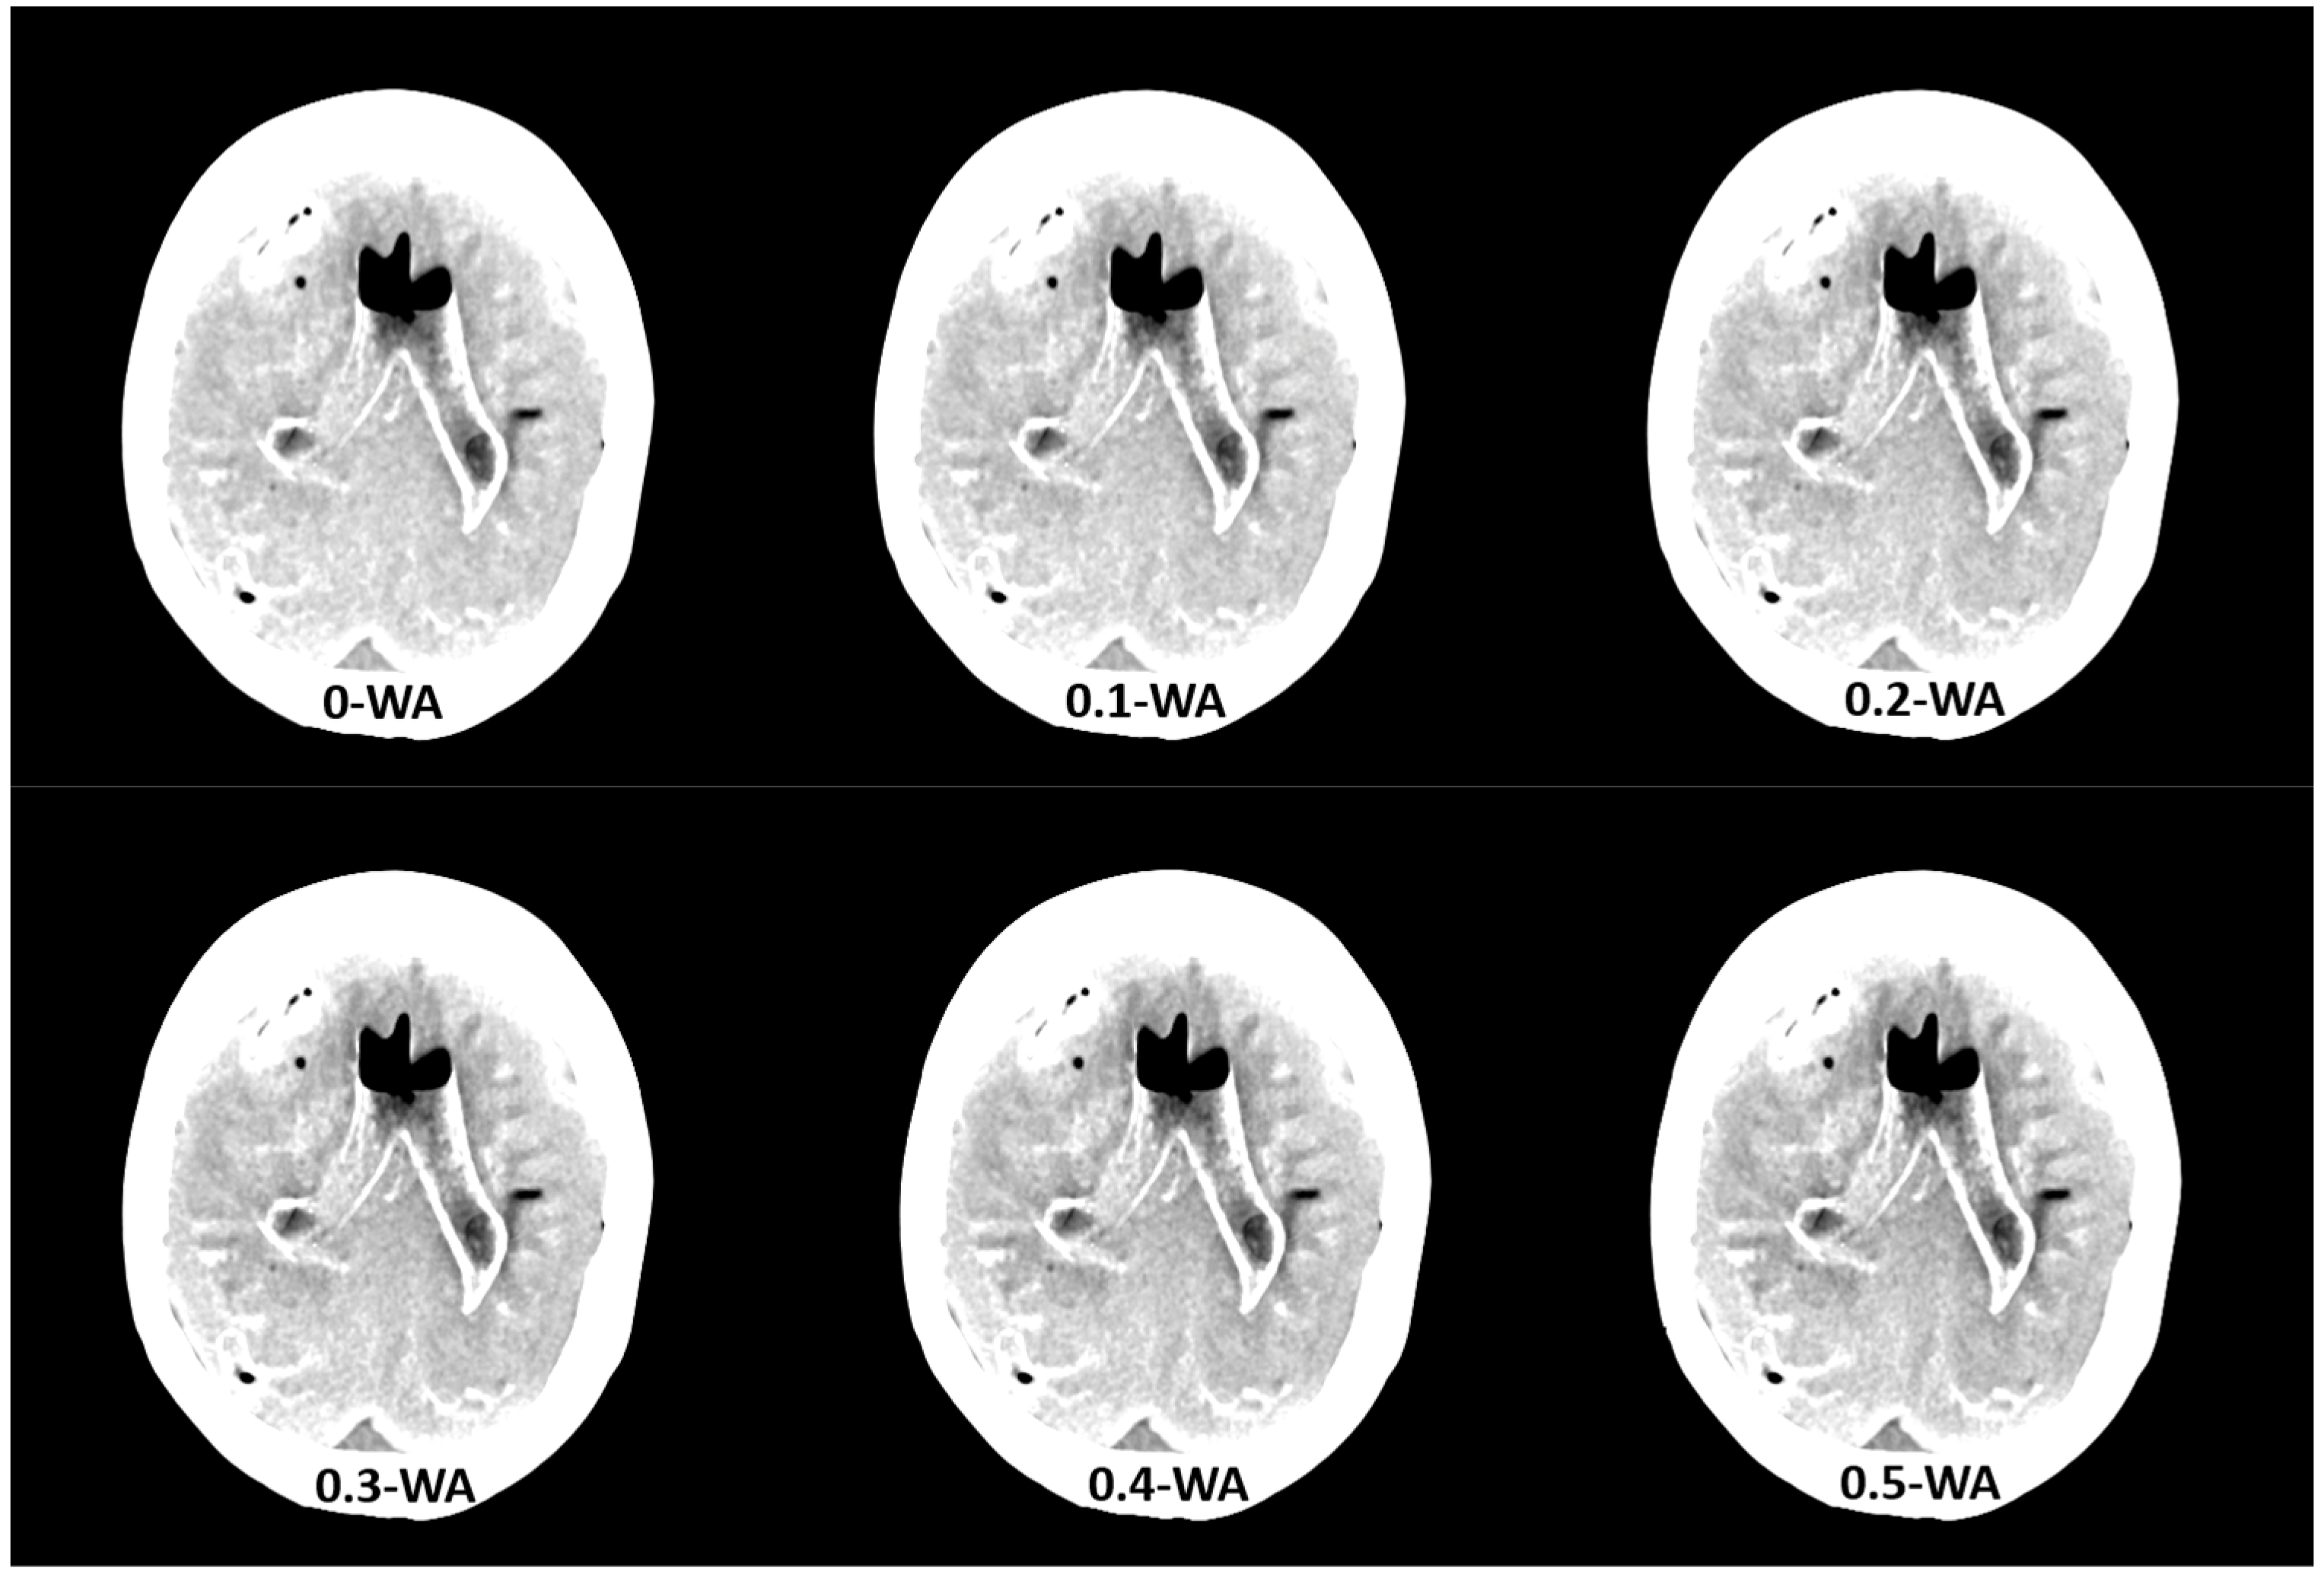

The qualitative assessment of the image quality of the 0.4-WA, 0.6-WA, and 0.8-WA patient reconstructions (Figure 5) was performed according to the methodology described in Section 2.1.3. of the phantom study.

Figure 5.

Weighted average (WA) image datasets of the brain with different weighting factors—0.4 (a), 0.6 (b), and 0.8 (c) of the same patient at the level of the frontoparietal lobe, basal ganglia, and posterior fossa. All images are displayed with the same window width and level (WW 80, WL 35).

The results of the qualitative analysis and image quality scores for all three readers, along with the results of the Friedman test with Bonferroni correction, are summarized in Table 6 and Figure 11. All readers found statistically significant differences in noise, SCA, and PFAI between all three WA image datasets. Reader 1’s results showed no significant differences in GM–WM contrast between the 0.4-WA and 0.6-WA images (p = 0.086), while reader 3 found no significant difference between the 0.4-WA and 0.8-WA reconstructions (p = 0.161). All three readers found that the overall IQ of 0.8-WA images was significantly lower compared to the 0.4-WA and 0.6-WA reconstructions. Two readers rated the overall IQ highest for 0.6-WA, with statistically significant differences compared to 0.4-WA and 0.8-WA (both p < 0.001). Reader 1 found the overall IQ of the 0.4-WA and 0.6-WA reconstructions equally superior to that of 0.8-WA (p < 0.001).

This study shows that the image quality of 0.6-WA image reconstructions is superior to the 0.4-WA images, which are generally recommended for the routine evaluation of non-contrast DECT of the brain. Quantitative and subjective analysis of phantom and patient images revealed that the optimal balance between GM–WM CNR, noise, and artifacts is achieved in WA reconstructions with 60% to 40% contribution of low-energy (80 kVp) and high-energy (140 kVp) datasets, respectively. While SECT provides an acceptable contrast-to-noise ratio, the 0.6-WA DECT reconstructions significantly outperformed the SECT proxy DECT reconstructions with 0.4 WF. This improved contrast between GM and WM increases the diagnostic accuracy of brain imaging, which is not as easily achieved with SECT.

Building on the phantom study, the patient study focused on 0.4-WA, 0.6-WA, and 0.8-WA image datasets. The quantitative analysis showed the same trend as in the phantom study—as expected, GM–WM CNR, SCA, and PFAI increased with higher WF. Although the absolute differences in CNR between the different WA image datasets are small, they are statistically significant and clinically relevant. Even small improvements in CNR can enhance diagnostic confidence, particularly in distinguishing subtle brain pathologies, as the inherent GM–WM contrast on CT imaging is small, with only a 5–10 HU difference in attenuation. Readers agreed that 0.6-WA reconstructions had the highest overall quality for image evaluation. We argue that a slight prevalence of low-energy data enhances GM–WM CNR while the contribution of high-energy data is still high enough to keep the artifacts at a reasonably low level. Although the routinely used 0.4-WA reconstructions, which are considered a proxy for standard SECT images at 120 kV, have fewer artifacts compared to 0.6-WA images, they are diagnostically inferior because they do not achieve sufficient GM–WM CNR, which is pivotal for detecting abnormalities in the brain tissue. On the other hand, although GM–WM CNR is higher in 0.8-WA images compared to 0.6-WA reconstructions, the artifacts affecting the analysis at the brain–bone interface (SCA) and posterior fossa (PFAI) significantly lower its overall diagnostic value. Moreover, all readers deemed 0.8-WA reconstructions to be significantly inferior to 0.4- and 0.6-WA images. These results are consistent with other studies that have shown that radiologists are more likely to prefer higher-contrast images, even at the expense of increased noise, over lower-contrast images with minimal noise artifacts [25,39].